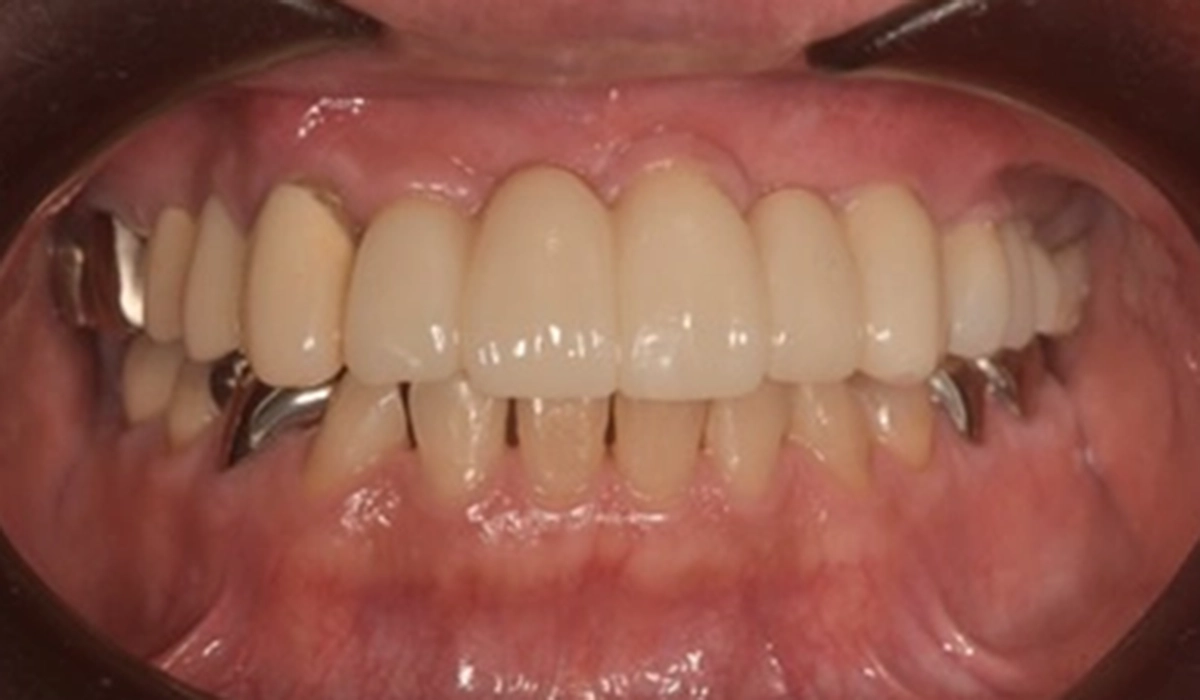

| 主訴 | 歯がぐらぐらしている |

|---|---|

| 診断 | 全体的な重度歯周炎による動揺 |

| 治療方針 | ご主人もインプラント治療で通われているため、インプラントによる治療を希望された。しかし、残せる歯は残したい思いが強かったため、将来を見据えた最小限のインプラントによる治療方針とした。 |

| 期間 | 9ヶ月 |

| 費用 | 2,716,000円 |

| メーカー | ストローマン |

| 治療後のリスク | 術後に痛みが出ることがある・術後に腫れることがある・かぶせものが割れたり、外れたりする可能性がある |